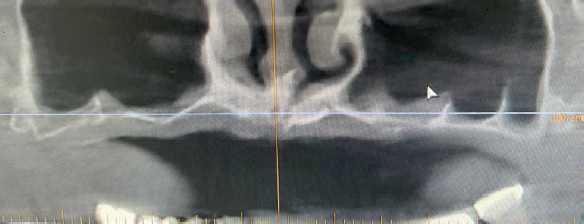

После анализа конкретной клинической ситуации, и оценки анатомических особенностей строения верхней челюсти (рис. 2) было принято решение об увеличении объема костной ткани в области гайморовых пазух и дна полости носа перед установкой имплантатов на верхней челюсти (рис. 3).

Рис. 2. Компьютерная томограмма верхней челюсти до начала стоматологического лечения

Fig. 2. Computed tomography of the upper jaw before dental treatment